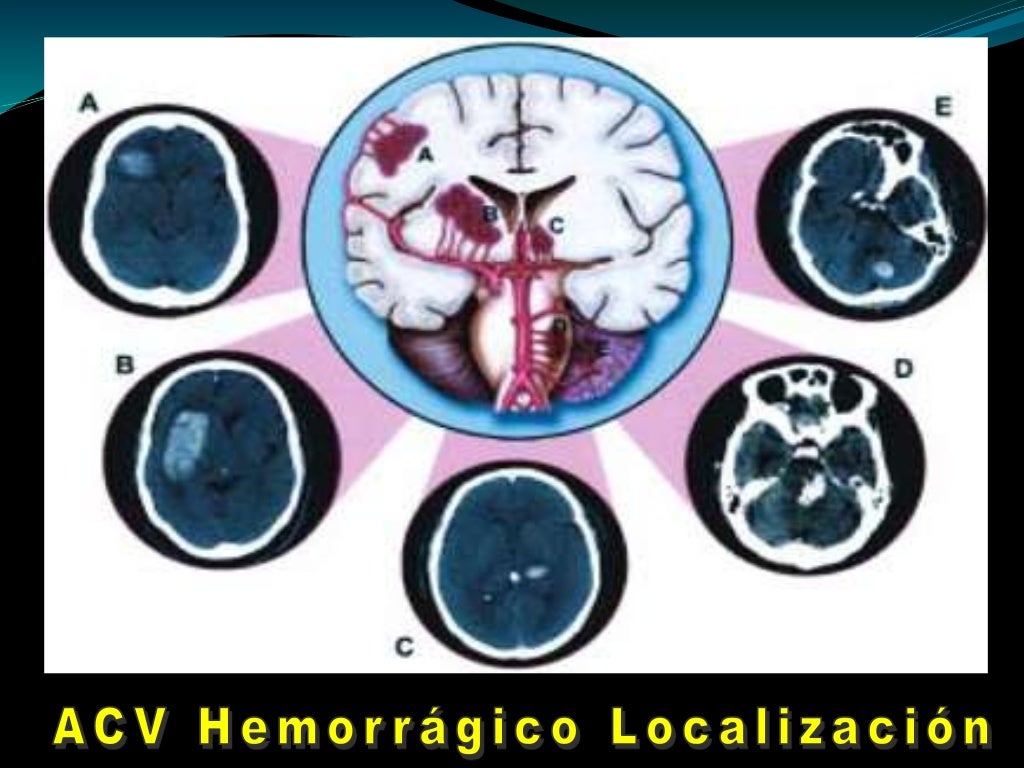

hemorragia cerebral Puede deberse a un trauma cerebral. The following 2 files are in this category, out of 2 total. Media in category intracerebral hemorrhage. La causa suele ser la hipertensión. Puede ser externo o dentro del cuerpo. Como ya se ha mencionado, suele estar relacionada con la hipertensión. Un hematoma intracraneal es una acumulación de sangre dentro del cráneo. En general, se distinguen entre hemorragias profundas (incluyendo aquellas que afectan a núcleos grises profundos de los hemisferios cerebrales), hemorragias.

Hemorragia Intracerebral subraquídea Neurocirugía de la Torre